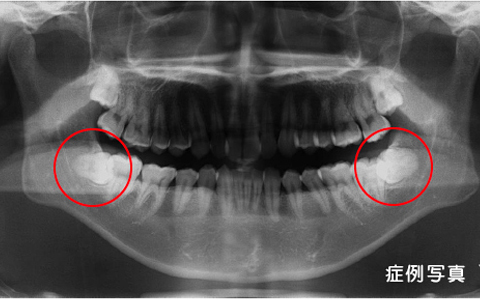

Wisdom tooth extraction親しらずの抜歯

親知らずは、全員はえてくるものではないことをご存じですか?

元々、親知らずがある人とない人がいるのです。

親知らずがある人の中で、他の歯と同様に物を噛むことに使える場合(かみ合わせに関係している場合)は、極度に虫歯が進行していない場合は抜く必要が無いことが多いです。

しかし、きちんと生えていない、横向きに生えているために掃除がしにくい、歯茎が腫れる・痛い、隣の歯が虫歯になるなど症状がある場合には抜く必要があるとお考え下さい。